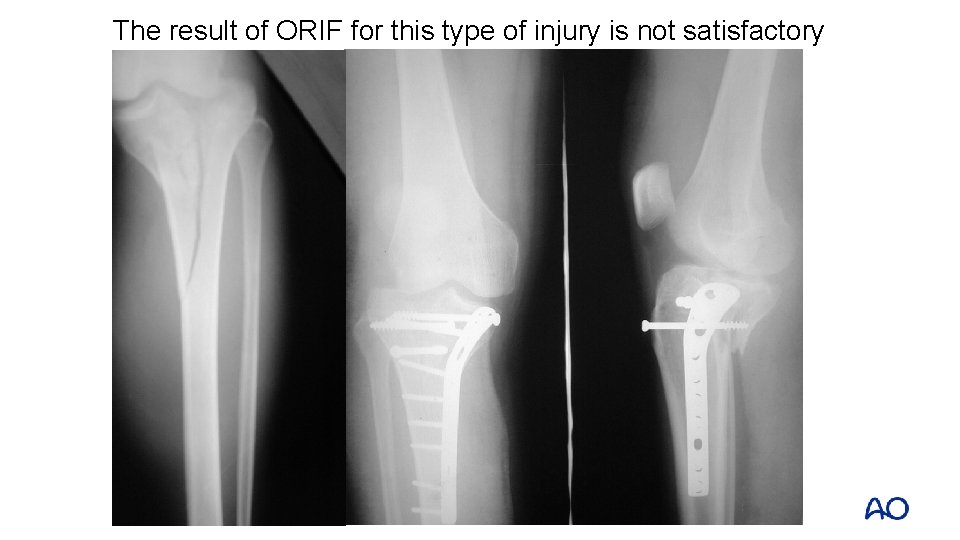

The result of ORIF for this type of injury is not satisfactory